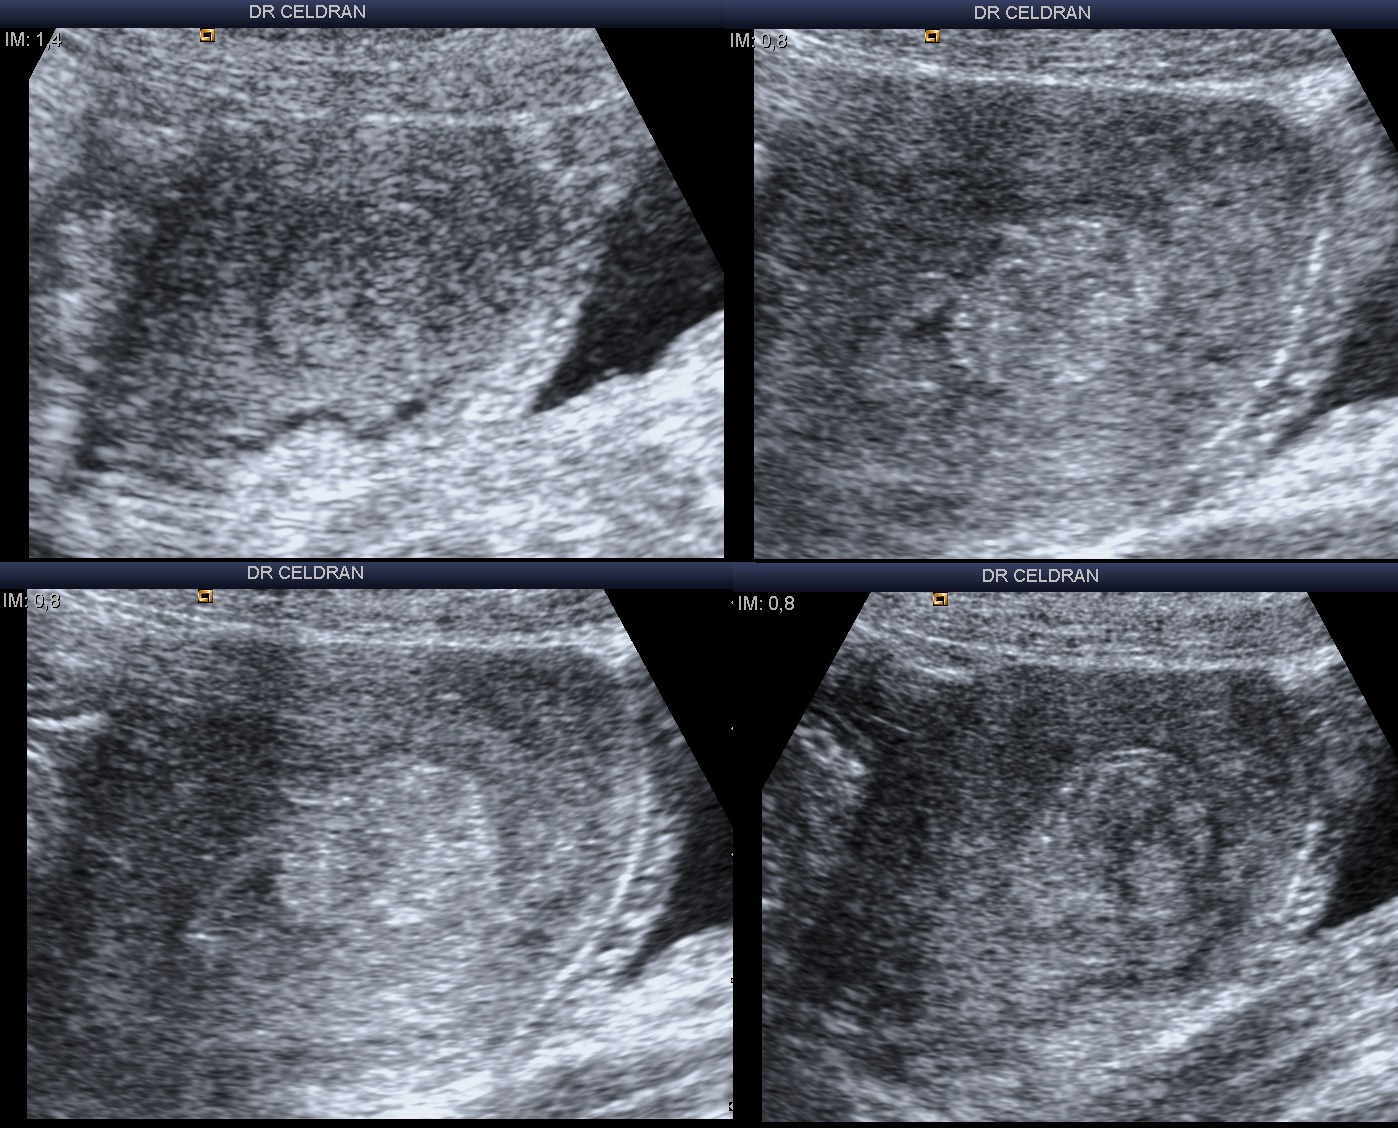

Controle de vacuité utérine par voie sus-pubienne à distance d’une IVG tardive (19 SA).

L’échographie (coupes sagittales) retrouve une image intra-utérine hyper-échogène, dicrétement hétérogène avec quelques cônes d’ombre sur certaines incidences, avasculaire au doppler couleur ou énergie, qui semble se distinguer d’une simple image d’endomètre épaissie : il existe, si on y prête bien attention, un fin liseré hypoéchogène entourant cette image, mais aussi un petit angle de raccordement avec la paroi utérine que souligne une petite image liquidienne à son pôle inférieur.

Rétention placentaire ?

Polype endométrial ?

Fibrome sous-muqueux ?

Une hystéroscopie est programmée et confirme le diagnostic de rétention placentaire.

Docteur CELDRAN Johann